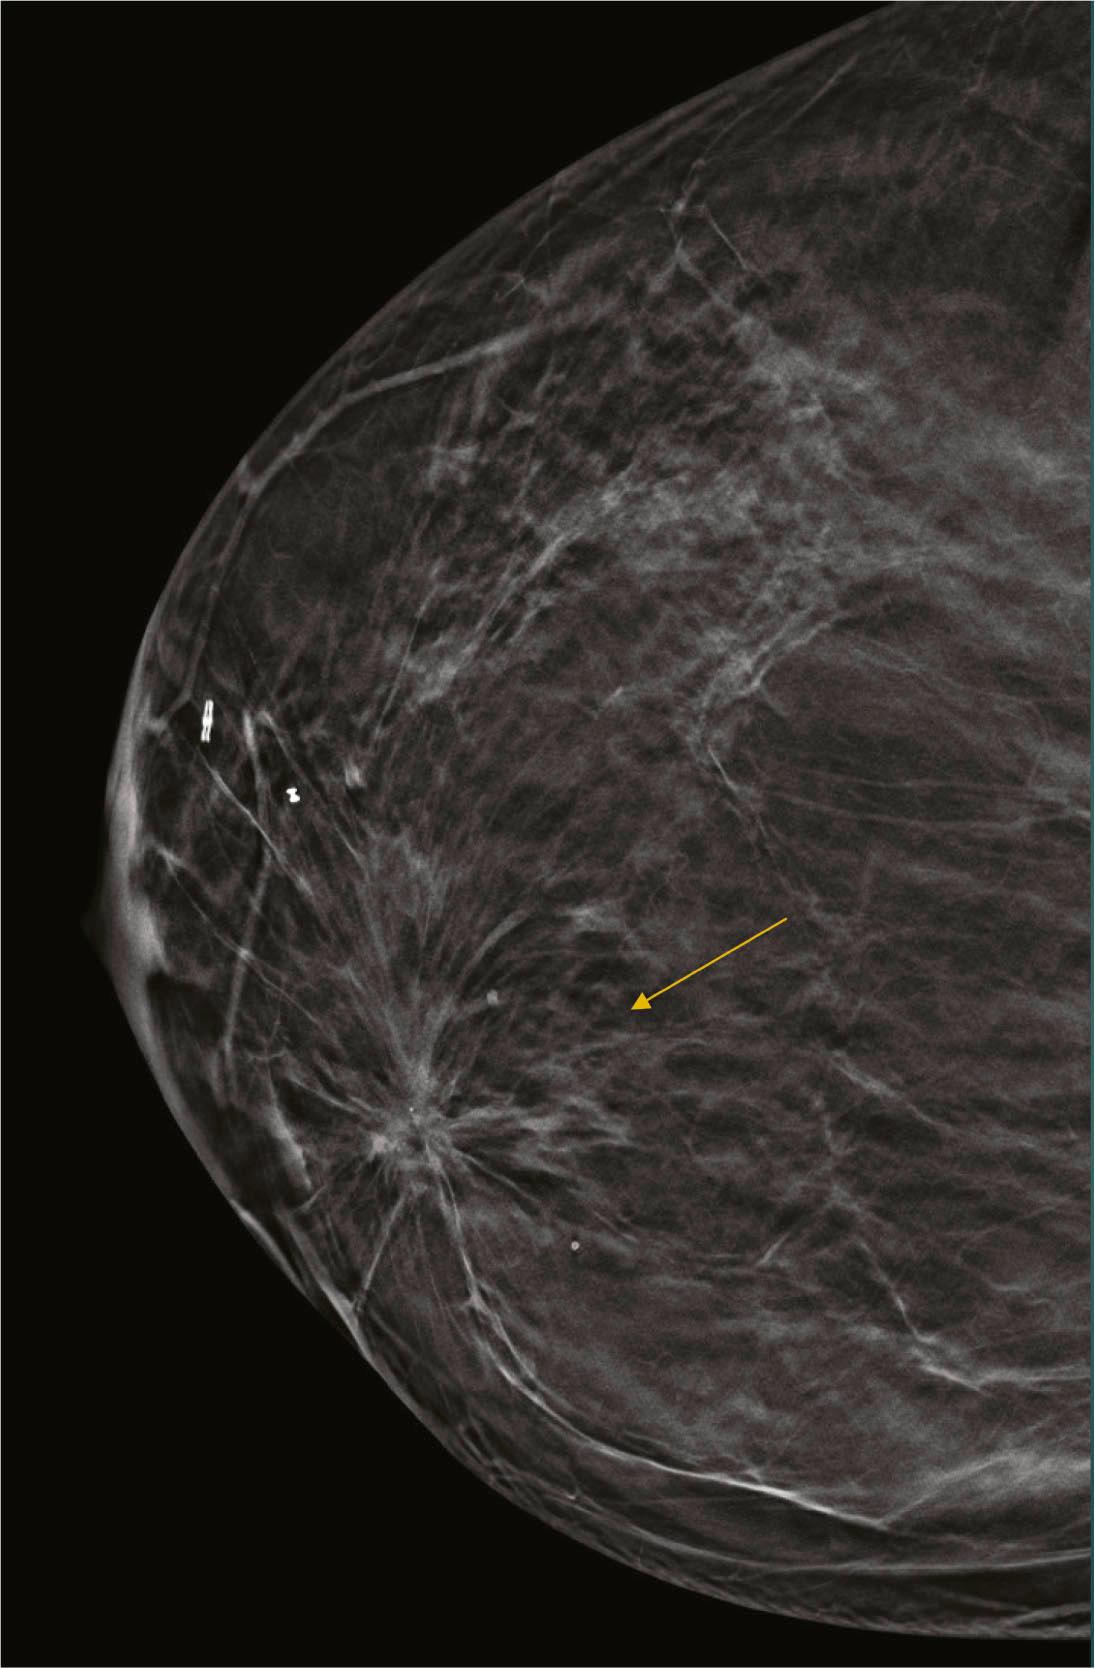

Architectural distortion is defined as disturbance of the normal architecture without an apparent mass. This appearance is most commonly the result of a surgical scar but can be attributable to a subtle invasive cancer, DCIS, radial scar, and other entities. Magnified views or tomosynthesis will better demonstrate the distortion and may reveal a subtle mass. Biopsy should be performed unless the area is shown to correspond to a surgical scar ( Fig. 8.7 ).

Fig. 8.7, Craniocaudal (CC) tomosynthesis image clearly shows the architectural distortion (arrow) due to lumpectomy scar.